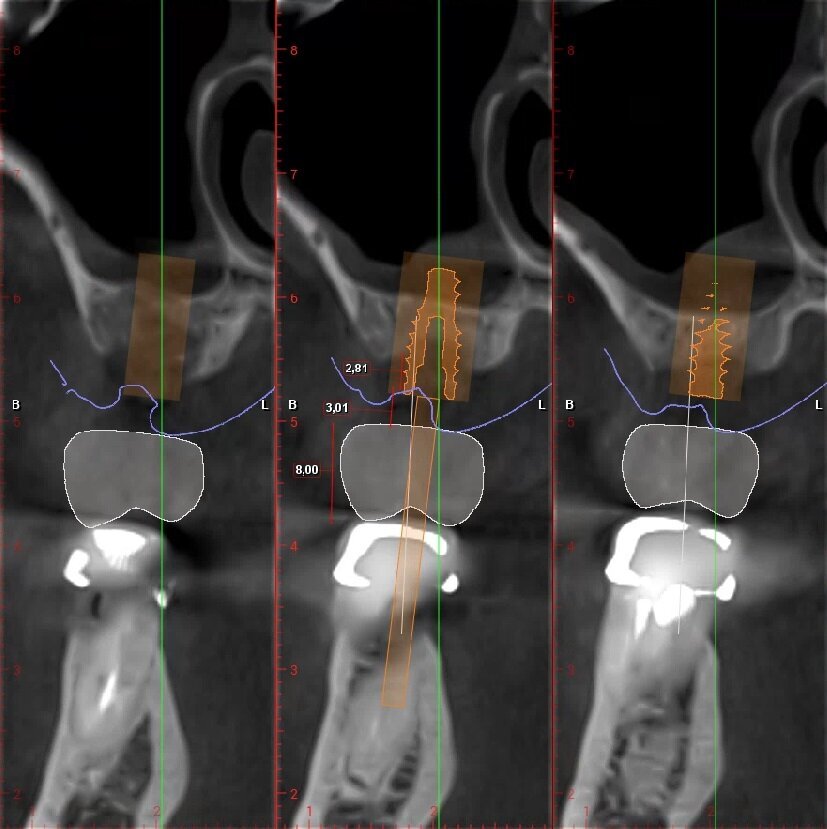

Fig. 5_Ceratura diagnostica elemento 2.6. Dimensione Corono-apicale della corona congruente con elemento controlaterale 8,00 mm, tragitto trans-mucoso 3,01 mm, entità della rigenerazione ossea verticale necessaria 2,81 mm.

_Pianificazione implantare

Posizionamento protesicamente guidato dell’impianto, tenendo conto dello spessore dei tessuti molli; che idealmente dovrebbe essere intorno ai 2-3 mm. Con valori più alti di 3-4 mm è indicata una ricostruzione ossea verticale al fine di riportarne la lunghezza in un range di normalità (Figg. 6, 7).

Fig. 6_Pianificazione implantare protesicamente guidata dell’elemento 2.5.

Fig. 7_Pianificazione implantare protesicamente guidata dell’elemento 2.6.